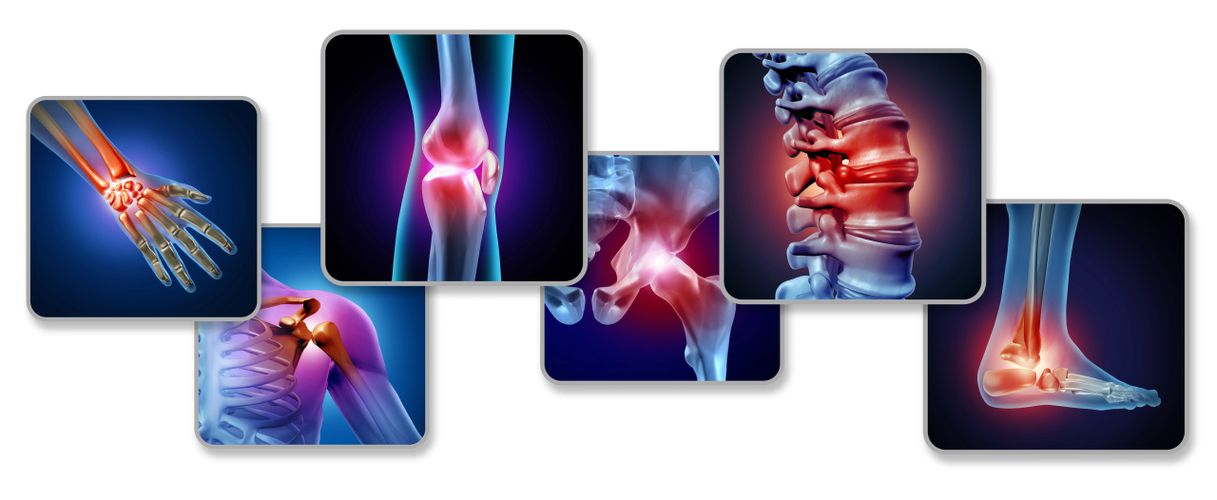

Natural Relief for Rheumatoid Arthritis, Chronic Pain, Back Pain & Stress

Rheumatoid arthritis can cause pain, swelling, stiffness, and difficulty in movement.

Sciatica can cause pain, numbness, and tingling that radiates from the lower back down the leg.

Spine-related problems can lead to pain, stiffness, poor posture, and limited movement.

Joint pain can cause discomfort, stiffness, and reduced movement in everyday life.

Neck pain can lead to stiffness, discomfort, and limited movement in daily life. At Chirokomphas, we offer natural, non-invasive care to help reduce pain, improve flexibility, and support better neck health.

Nerve compression can lead to pain, numbness, tingling, and weakness in different parts of the body.

Chronic pain can interfere with comfort, movement, and quality of life.

Muscle stiffness can cause tightness, discomfort, and reduced flexibility.